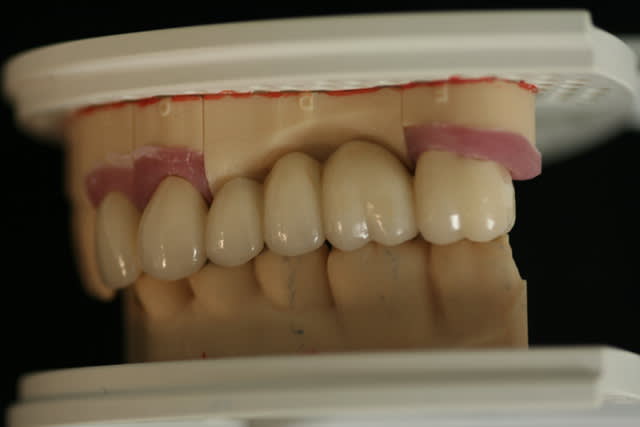

depuis janvier je ne travail plus qu'en connect ,plus d'élastomer

sur la photo "maquillage" on voit que le bord du provisoire a été un peu envahissant sur la canine, avec le bridge définitif la gencive est revenu a sa place, avec des bords foireux la gencive ne revient pas

Joli bridge.